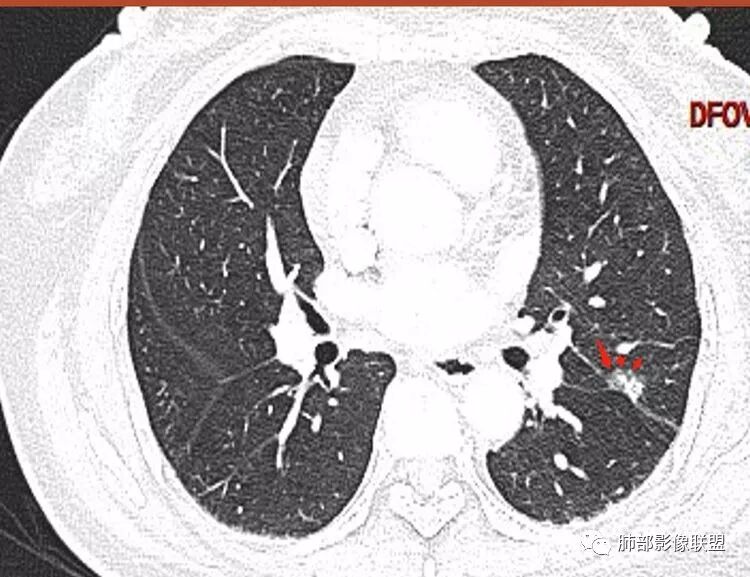

马宁强:考虑肉芽肿性病变,隐球菌可能彭君:左肺上叶舌段混合毛玻璃密度结节 边缘清 有分叶毛刺 斜裂胸膜凹陷征 考虑腺癌可能王秀仙:左肺上叶结节,部分边缘磨玻璃清晰,有分叶毛刺,支气管通过并扩张,其外侧小叶间隔不规则增厚,胸膜牵拉,考虑腺癌。鉴别慢性炎症。田园晚风:左肺上叶多个小结节融合呈分叶状,可见叶间裂牵拉,考虑腺癌张帅:左肺上叶后段结节,内可见支气管穿过,病灶周围有少许毛刺,病灶边缘有浅分叶,对叶间胸膜有牵拉,部分位置呈对叶间胸膜推移。考虑为恶性病变,腺癌?。杨泽锋:混合型磨玻璃结节,边缘有膨隆、有凹陷,明显的胸膜牵拉,考虑腺癌可能大;内部支气管通畅、似乎有鬼脸征,所以鉴别隐球菌Lotus:病灶内部有结节感,这个大小似乎是次级肺小叶的大小,考虑炎性,有冠位最好了。但是胸膜牵拉有些恶性提示心包右侧软组织密度影考虑心包隐窝Yiren Sishui(厶水伊人):叶间裂有膨隆有凹陷,考虑恶性,腺癌可能

徐婕:同意恶性腺癌可能岁月:女,56;空泡,分叶毛刺,牵拉线,胸膜凹陷征,有强化,浸润性腺癌。THINKER:左舌见结节,膨胀为主,部分收缩,分叶丶短丶硬毛刺,牵拉斜裂,有小空泡,支气管穿行,有强化,常规腺癌丽:左肺上叶近胸膜下结节,胸膜牵拉,边缘膨隆,并可见深分叶及毛刺,内有空泡,增强后可见强化,倾向腺癌淘时光:混合磨玻璃结节,实性部分较多,内见支气管穿行,腺癌首先考虑了…☀:左肺上叶结节影,实性,边缘分叶征,其内可见空泡,部分膨胀生长,局部叶间裂牵拉上移,叶间裂光滑增厚,首先考虑肿瘤黄棘:左肺上叶结节,边缘彭隆, 周围磨玻璃影边界清,内部可见扩张支气管,叶间胸膜牵拉,考虑腺癌心灵鸡汤:左肺上叶舌段近斜裂处混合性结节,以实性成分为主,有分叶、毛刺,牵拉邻近叶间、脏层胸膜,增强有强化,影像学上看偏恶性,分类LU-RADS 4C类,MIA浸润性腺癌可能,鉴别肉芽肿性病变、隐球菌,请老师指点!THINKER:这个如果是腺癌,应该是IAC了,过MIA了,个人看法,罗老师一切∮随缘:左肺叶裂胸膜下结节,边缘收缩弱,周围有GGO,边界清楚,形态欠规则,其内似有支气管穿行,增强扫描轻度均匀强化,考虑1肉芽肿性病变(隐球,炎性假瘤)2:浸润性腺癌Clover:考虑腺癌,实性为主混合有少许边界清晰ggo,边缘膨隆,其内支气管气象不规则,有收缩力。Coke with ice:还有一个疑问请教一下:这个是混合磨玻璃结节还是实性结节?个人倾向于后者。心灵鸡汤:有部分磨玻璃Coke with ice:实性结节周围GGO初学者:实性,周围有毛玻璃晨:有浅分叶,有毛刺,有叶间裂牵拉,内有囊泡,考虑腺癌。初学者:稍等,我等会开电脑看,但是感觉和你们一样,感觉是一个典型病例来着Coke with ice:这个人我也倾向于腺癌。但是诊断腺癌还有一个比较疑惑的地方,肺窗病变密度显示比较实,但是纵隔窗病灶范围明显比肺窗小,腺癌可以解释的通吗?张小兵:混合磨玻璃结节,内见支气管穿行,分叶,胸膜牵拉从凹陷处进入,腺癌首先考虑小微:

晨读结果:病理是微浸润腺癌